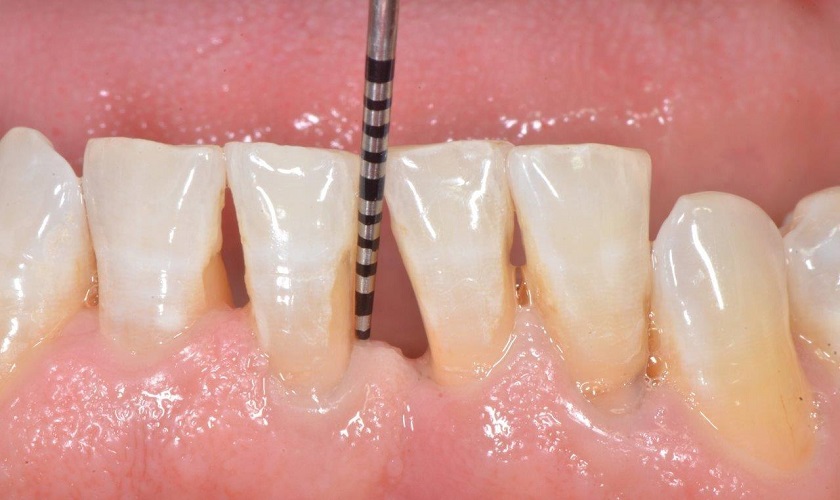

Tụt cổ chân răng(hở cổ răng, hở chân răng, tụt lợi chân răng) là tình trạng các mô lợi xung quanh răng bị mòn. Hoặc mô lợi bị kéo tụt ngược trở lại từ bề mặt răng. Đây là bệnh lý răng miệng khá phổ biến, có thể gặp ở nhiều độ tuổi khác nhau. Trong đó, tỷ lệ bị tụt chân răng nhiều nhất là người ở độ tuổi trung niên.

Giai đoạn này có thể nhìn thấy bằng mắt thường và thường xuyên bị ê buốt răng. Lúc này bạn cần xác định nguyên nhân để có phương án điều trị triệt để. Đa số nguyên nhân gây hở chân răng đều có thể điều trị bằng cách ghép vạt lợi để phục hồi lại phần lợi.

Dựa vào mức độ tụt như thế nào, cấu trúc răng, số lượng răng và vị trí mà bác sĩ sẽ có đánh giá và đưa ra phương án chữa trị phù hợp. Nếu bạn bị tụt lợi do mất răng lâu ngày làm tiêu xương thì bác sĩ sẽ chỉ định ghép xương trước. Sau đó cấy ghép Implant để phục hình răng đã mất. Tiếp theo bác sĩ sẽ kiểm tra tình trạng xem có cần ghép vạt lợi hay không.